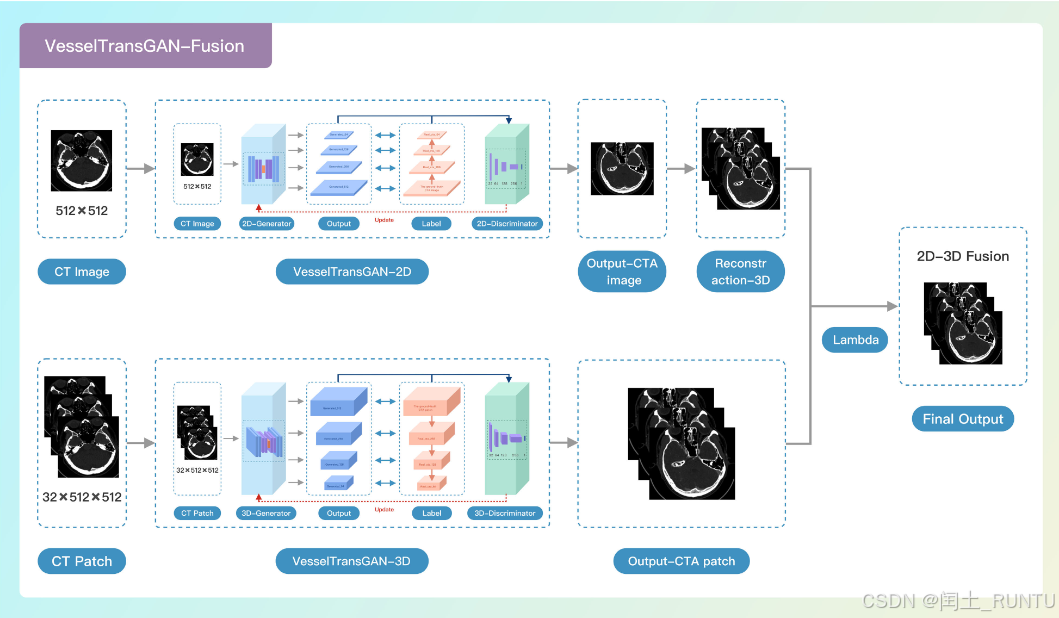

2. 2D-3D融合策略

(1)整体工作流理解

文中提出了2D和3D两个版本的网络,生成结果也有2D和3D两种形式。

按照文中的说法,2D模型是单层输入,单层输出,图像细节更好,但层与层之间的连续性差,而3D数据特点刚好相反。因此为了兼得鱼和熊掌,需要一种融合策略将二者融合。

上图是整体的工作流,分别由2D网络和3D网络得到结果,经过融合后得到最终结果。

举个例子:例如一个NCCT体数据共有32层,每层尺寸为512×512;2D网络单张输入,单张输出,最终得到32张独立的生成结果;3D网络则是将32张数据同时输入,然后一起输出32层数据的生成结果,最后再通过文中提出的融合策略将两者融合。